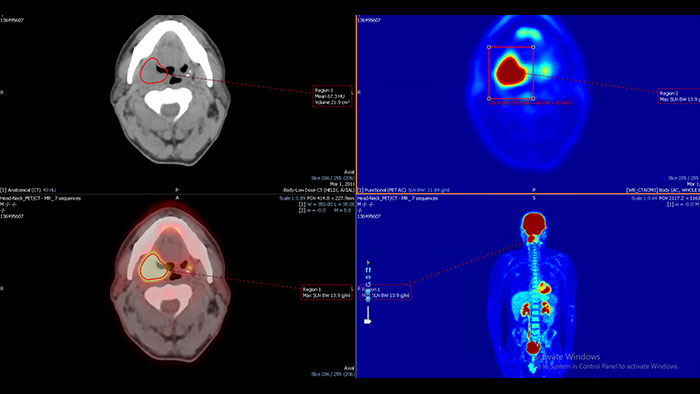

Assessing Amyloid plaque

The NM NeuroQ Amyloid analysis tool is designed to help clinicians to assess the presence or absence of Amyloid plaque in the brain. Provides quantitative analysis tools for Brain PET scans using NeuraCeq or Amyvid agents.

Benefits